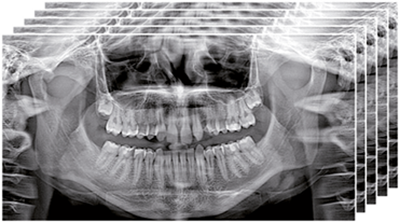

Высококачественная 2D-визуализация, полученная с помощью множества расширенных функций для более эффективной диагностики. Он обеспечивает детализацию изображений благодаря чувствительности недавно разработанного CMOS сенсора. GO 2D/3D предлагает быструю и точную диагностику с помощью нескольких программных опций для сбора изображений, предназначенных для получения высококачественных 2D-изображений для всех диагностических нужд. Отличные, четкие и подробные панорамные изображения с технологией ApT (Авто адаптивные обработки изображений). Функция aPAN (адаптивное панорамирование) позволяет получать пять слоев панорамных изображений за одно сканирование, чтобы выбрать наиболее подходящее для объема исследования.Совершенство в 3D

Вы получаете детализированные изображения благодаря чувствительности новейшего датчика CMOS. GO 2D/3D предлагает быструю и точную диагностику с несколькими программными вариантами получения снимка, разработанными для съемки высококачественных 2D изображений для любых диагностических задач. Отличные, четкие и подробные панорамные изображения благодаря технологии ApT (автоадаптивная обрботка картинки). Функция aPAN (адаптивное панорамирование) позволяет снимать пять слоев панорамных изображений за одно сканирование и выбрать наиболее подходящее для цели обследования.